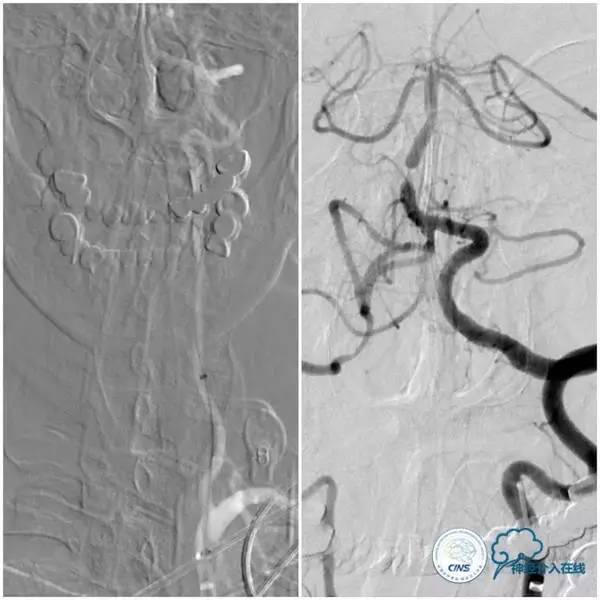

扩张后沿微导丝送入Apollo支架(2.5mm×8mm),释放支架后造影显示支架贴壁良好,狭窄明显改善,前向血流TICI3级(图9,10)。

图9

图10

1.治疗基底动脉狭窄时,如果双侧大脑后动脉P1段发育不良或缺如,选择粗大的小脑上动脉作为微导丝的着陆区还是可行的,但要避免输送系统时导丝前窜穿孔危险。

2. 本例狭窄程度重且病变短,治疗过程中担心病变过硬导致直接放置球囊扩张支架移位,故选择预先球囊扩张。